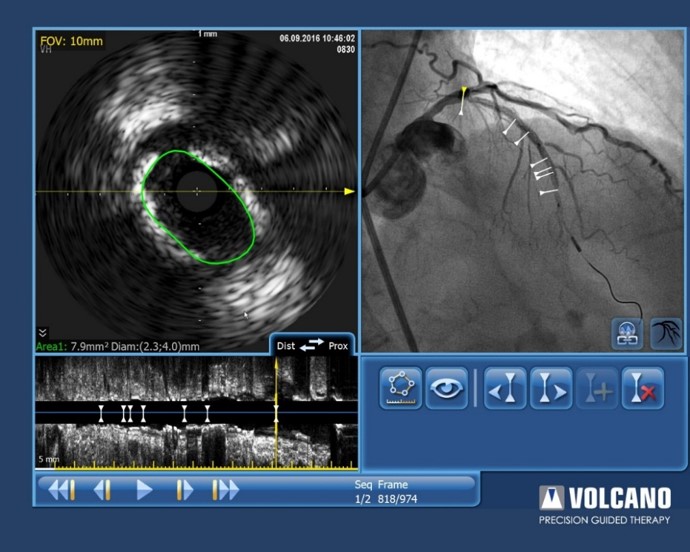

Nachdem ein Stent medial im Gefäss plaziert wurde, musste die behandelnde Person nun entscheiden, ob der proximale RIVA ebenfalls zu behandeln sei. Die Tri-Registrierung konnte dem fraglichen Segment einen iFR-Wert von 0,98 sowie eine Schnittfläche von 7.9mm² im IVUS zuordnen.